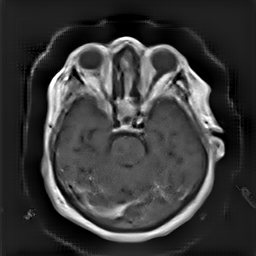

(a) Guide 𝑮𝑮\boldsymbol{G}

Refer to caption

(b) Input 𝑰𝑰\boldsymbol{I}

(c) Guidance map 𝑴𝑴\boldsymbol{M}

(d) Prediction 𝑷𝑷\boldsymbol{P}

(e) Ground truth

(f) Guide 𝑮𝑮\boldsymbol{G}

(g) Input 𝑰𝑰\boldsymbol{I}

(h) Guidance map 𝑴𝑴\boldsymbol{M}

(i) Prediction 𝑷𝑷\boldsymbol{P}

(j) Ground truth

Figure 2: Inputs and outputs of the guided filtering pipeline based on the WDSR network. T1 & T2 MRI pairs (a)-(e) and CT & MRI projection images (f)-(j).

In Fig. 2 and 4, exemplary input, output and label images of the pipeline are presented for both tasks. Additional super-resolved images for both network architectures with and without the guided filter can be seen in Fig. 3. The results show a consistently high quality over both, the tomographic and the projective domain, as well as both tasks. Corresponding quantitative evaluation can be found in Table I and II. For SR, the WDSR network, i.e., the designated super resolution network, performs consistently better for both datasets with and without the guided filter. Applied to the tomographic images, the approaches without the guided filter deliver slightly better quantitative results. For the projection images this difference diminishes and both approaches are on par. In the case of denoising, the approaches with the guided filter deliver a lower mean absolute error while the structural similarity is increased without it. Though, the measurable differences are only marginal. The results generated by the plain guided filter without the learned guidance map are numerically worse than the approaches empowered by the guidance map generator for all tasks. This observation is most prevalent when observing the results of the tomographic T1 and T2 Flair images for SR, while for denoising the results are closer to the deep learning-based approaches.

In general, the decrease in image quality metrics w.r.t. to smaller radii is much stronger for the tomographic T1 and T2 Flair images than for the projection images. We assume the reason for this to be the difference in resolution of both datasets. The projection images resemble the ground truth more closely from the outset when compared to the tomographic images as seen in Fig. 2(b) and 2(g), respectively. Consequently, more information has to be generated by the networks. As the guided filter is sensitive towards correlation between the input and guidance map the constraints on the applicable changes are more severe.